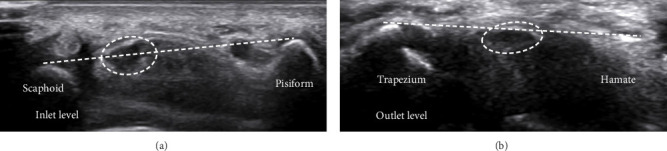

目的:本研究旨在评估各种超声标准对腕管综合征(CTS)严重程度分级的价值。方法:由经验丰富的放射科医生对确诊的CTS患者进行超声评估,对NCS结果不知情。测量旋前方肌横截面积(CSA)、腕管进出口、回声性、屈曲时的横向运动、压平率和屈肌支持带增厚。结果:正中神经回声减弱是轻度和中度病例的显著特征。神经运动减少在严重的CTS病例中更为普遍。两组正中神经压平率和屈肌视黄带厚度无显著差异。进气道弯曲有显著性差异。进口和出口的CSA显示严重的CTS,差异有统计学意义。结论:虽然正中神经压平率和屈肌视黄带厚度无明显差异,但超声多指标对准确诊断和治疗具有重要意义。

Objective: This study aimed at assessing the value of a variety of ultrasound criteria for grading carpal tunnel syndrome (CTS) severity. Methods: Ultrasound evaluations were conducted on confirmed CTS patients by an experienced radiologist, blinded to NCS results. Cross-sectional area (CSA) at pronator quadratus muscle, carpal tunnel inlet and outlet, echogenicity, transverse motion during flexion, flattening ratio, and thickening of the flexor retinaculum were measured. Results: Decreased echogenicity of the median nerve was notably observed as a distinguishing feature between mild and moderate cases. Decreased nerve movement was significantly more prevalent in severe CTS cases. No significant differences were found in the median nerve flattening ratio or flexor retinaculum thickness. Bowing at the inlet showed significant differences. CSA at the inlet and outlet indicated severe CTS with significant differences. Conclusion: The findings highlight the importance of using multiple sonographic criteria for accurate diagnosis and treatment, although no significant differences were noted in the median nerve flattening ratio and flexor retinaculum thickness.